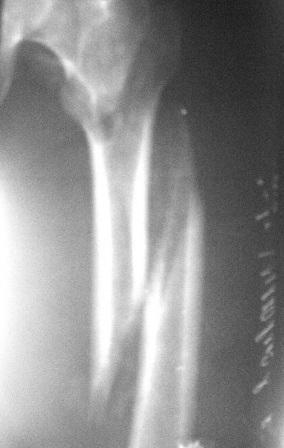

Больному 50л. В отдаленном от центра р-не ДТП 6.12.08г. д-з " тяжелая

ЧМТ, мн. переломы ребер слева, отрыв ножки селезенки, повреждение п/ж

железы, з/двойной перелом прав. бедра.После экстрен. хирургических

вмешательств, конечность фиксирован кокситной гипсовой лонгетной

повязкой. Кома 2 нед, нагноение п/о раны живота, постравмат.

пневмония.

20.01.09г. переведен к нам. Постельный больной,

ослабленный, бледный, весом 56кг:  свищ п/о раны перед.брюшной стенки

с сукровичным выделением, гипс снят - деформация и укорочение

бедра на 6см, в обл перелома есть спайка. Слабо, но активно поднимает

ногу, контрактура т/б и коленных суставов.

Вложение не в текстовом формате было извлечено…

Имя     : PICT0013.JPG

Тип     : image/jpeg

Размер  : 14523 байтов

Описание: отсутствует

Url     : http://weborto.net:8080/pipermail/ortho/attachments/20090125/3084e8b8/attachment-0004.jpeg